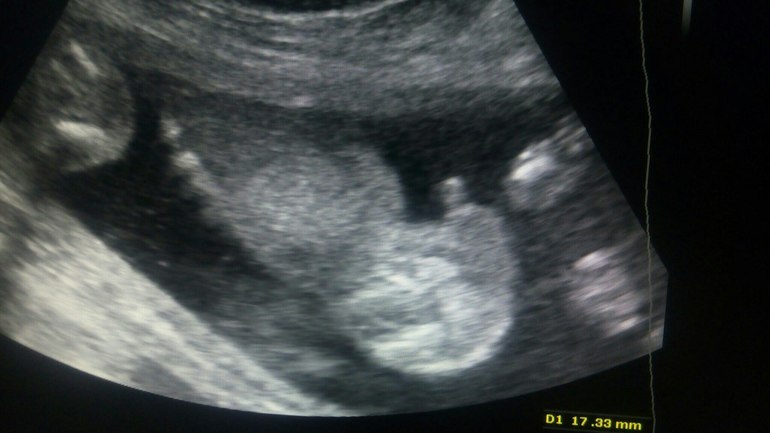

15+3 пол. мальчик?

Пол малышаДевочки, кто делал узи в 15 недель и кому сказали, что мальчик скиньте плиз снимки узи. Мне сегодня сказали что мальчишка у нас на 100%. Очень интересно сравнить.

Сделали фото:

В этом году рожу сыночка❤️